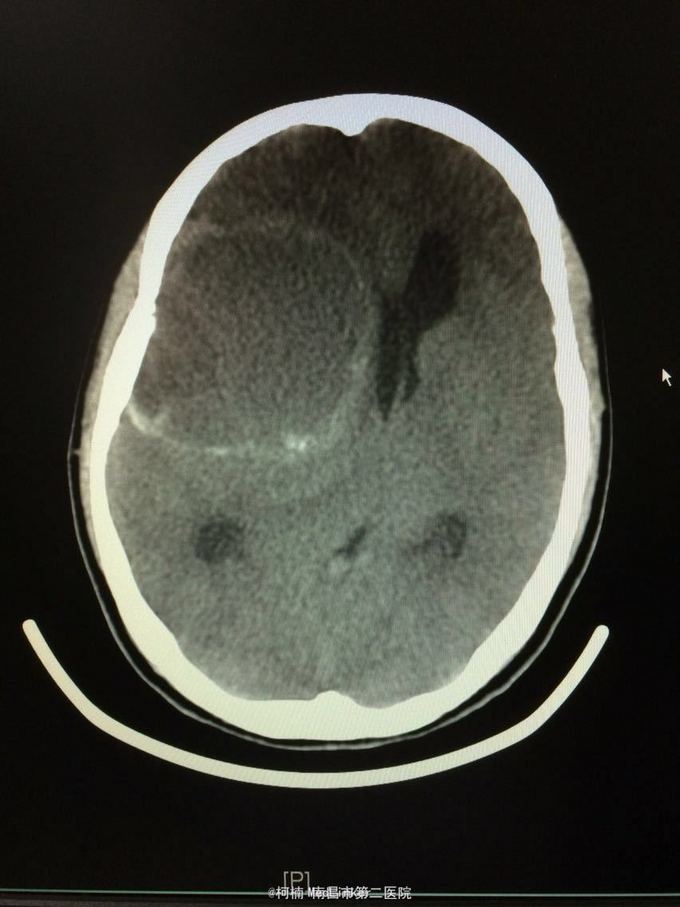

主诉:头痛2年,加重2月 病史:2年前无明显诱因出现头痛,主要为右侧额颞叶胀痛,近两个月来上述症状加重,遂至当地医院行头颅CT提示:右侧额颞叶类圆形异常信号,考虑脑膜瘤合并出血。

神经系统查体阴性 辅助检查:头颅CT提示右侧额颞骨板下肿物伴瘤卒中考虑脑外源性脑膜瘤

右侧额颞脑膜瘤 处理:全麻下行右侧额颞叶占位性病变切除术,术后病理提示:血管型脑膜瘤,WHO1级